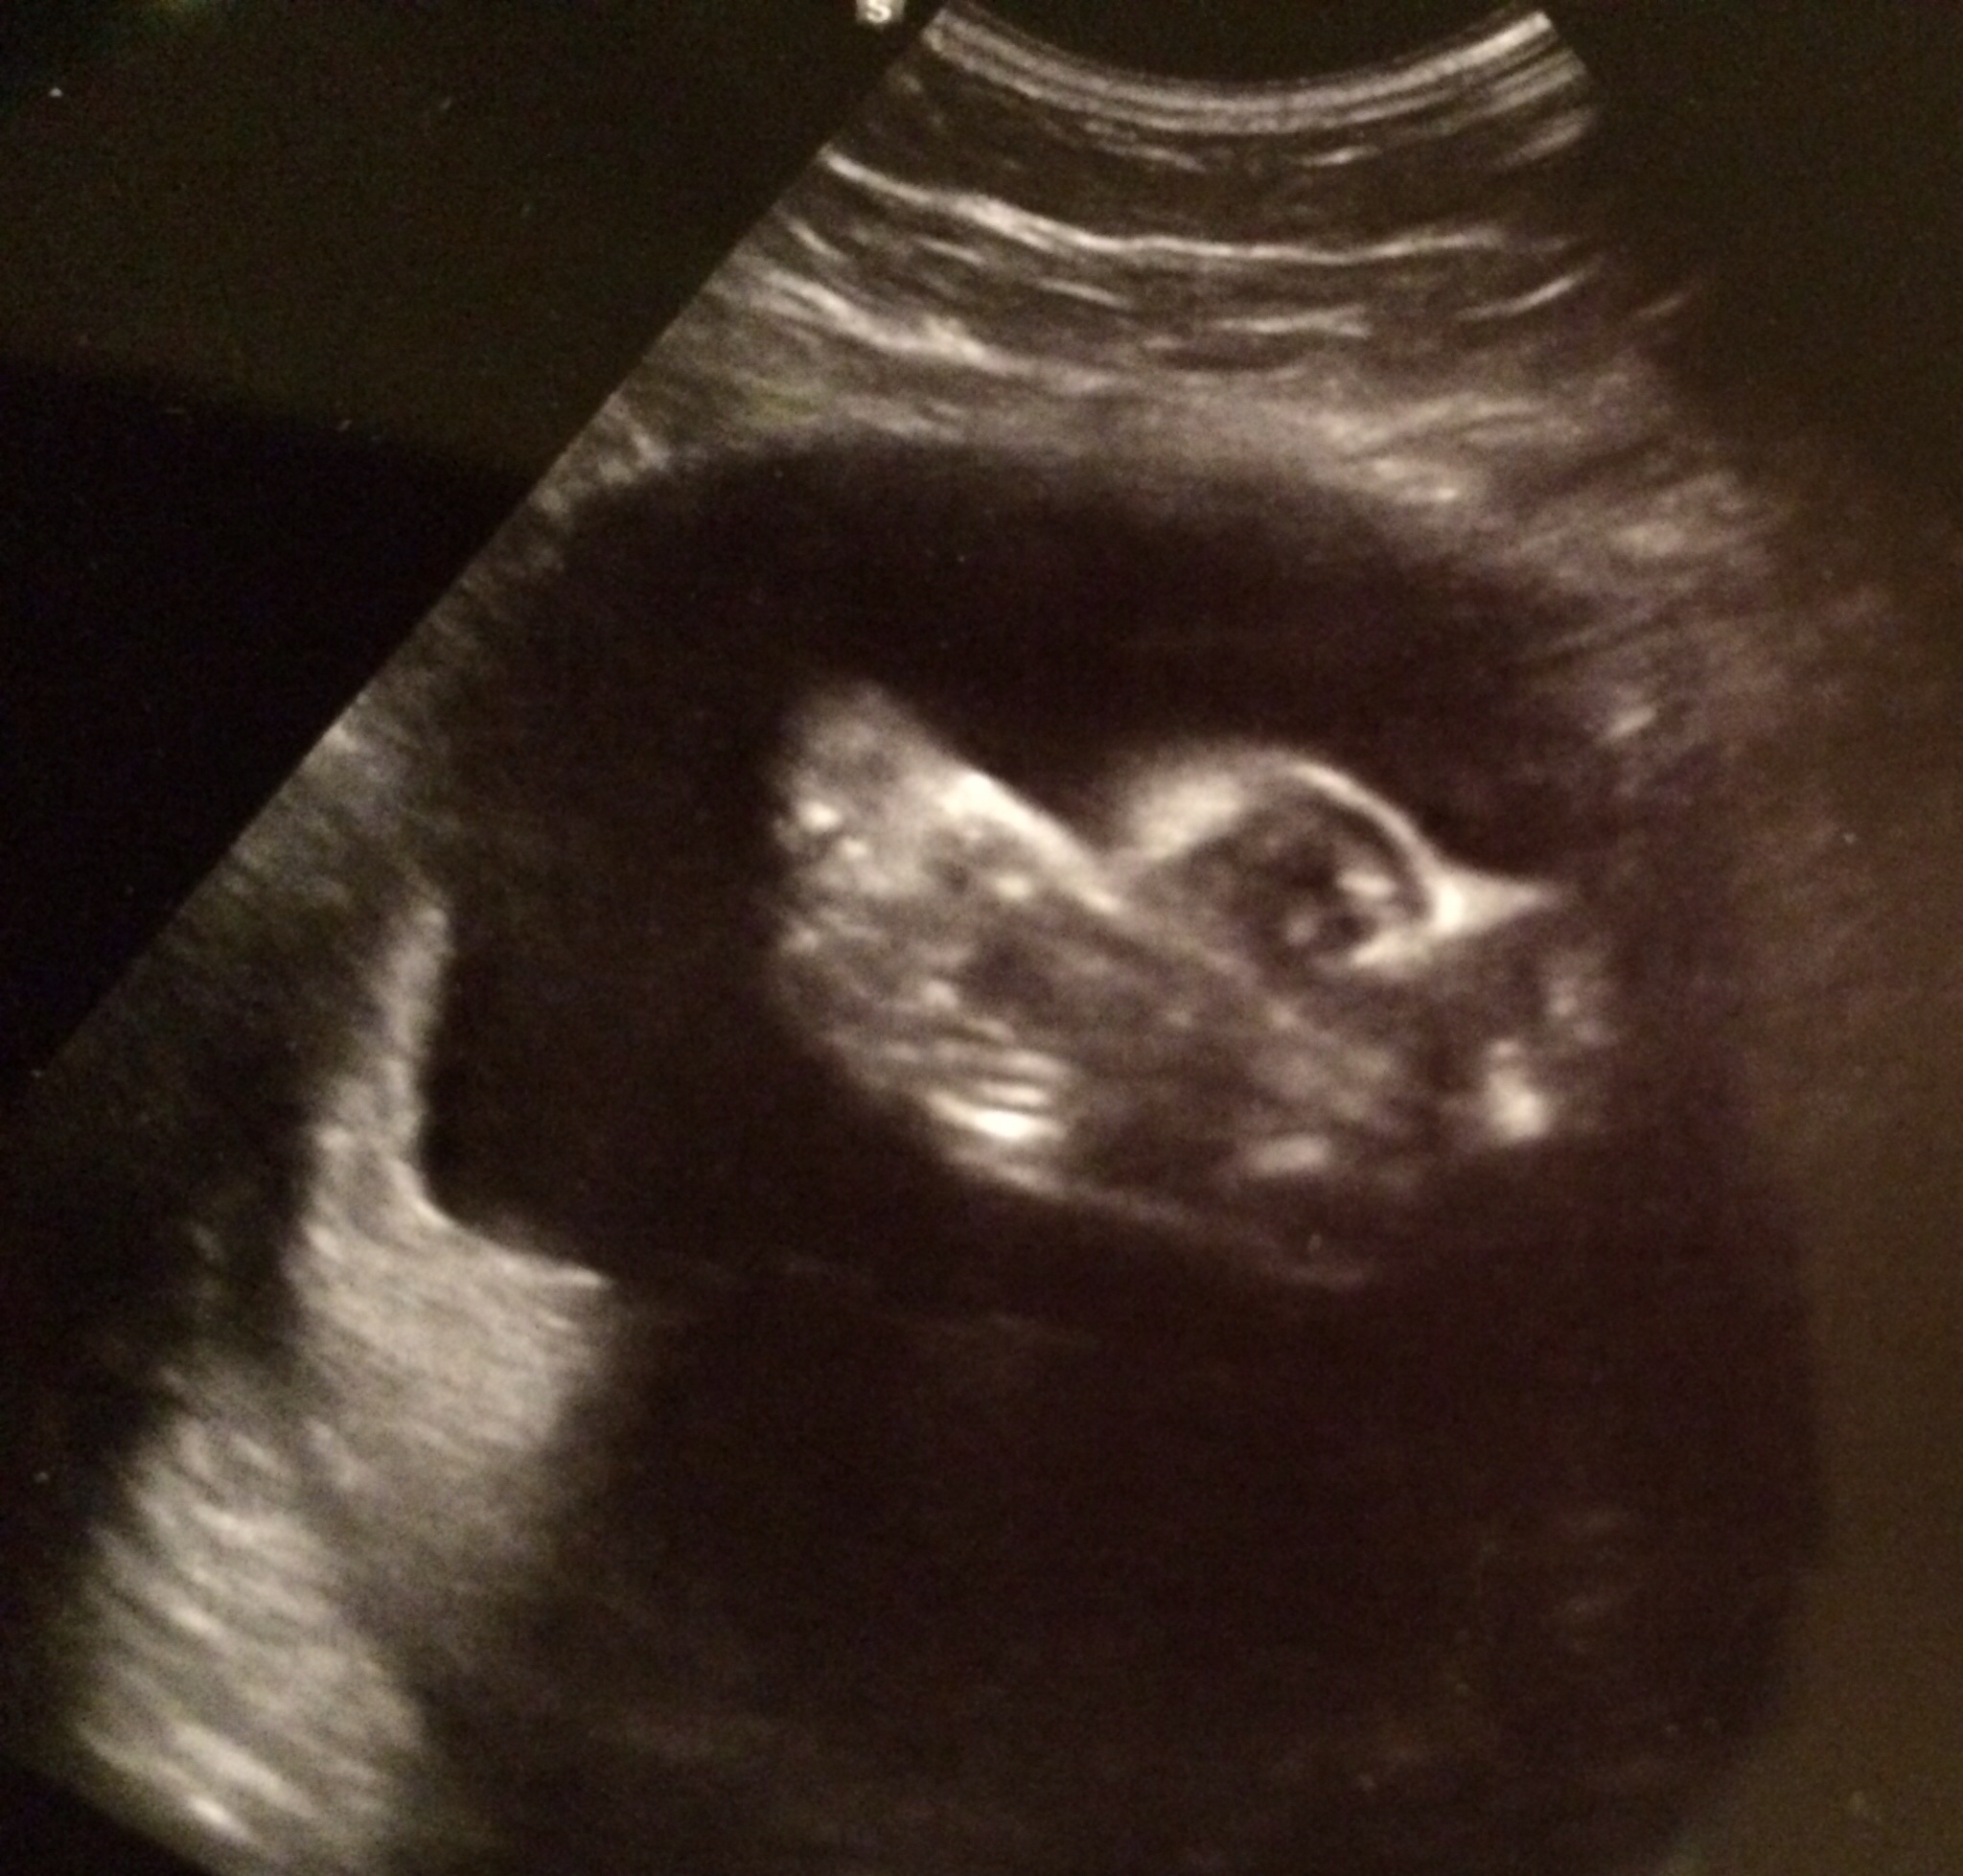

So today I was seen at about 1030 for another ultrasound. This was kind of nice because I had an ultrasound tech and she let me see Skippy's face -- BIIIIIG yawn, so cute! -- before looking at the important bits--her heart. And she gave me some pictures. Of course, the arrhythmia showed up so she went and got the doctor so he could take a look. He looked at her heart and watched the arrhythmia for a while and said the same thing everyone else has been saying. But he added that if it doesn't resolve by the time I go into labor, they can't usually tell how the baby's heart is handling labor, which leads to c-section... But he said that was unlikely. ? I don't know.

So he takes me back to ultrasound and gets a good look at her. Looks at all her parts and they looked amazing and perfect (I could see her on this ultrasound, I couldn't on the last one). But the pre atrial contractions are just occurring a lot. He is a specialist and also thinks she will grow out of it as most babies do, if not by birth, then shortly after. However, he wants to monitor her closely. He said if her beat switches to tachycardia (fast) because of stress, then it's a problem. But he feels this is is unlikely to happen, as it usually doesn't. He wants me back for another ultrasound the next day (which was today), and then 3 times next week.

Had US all seems good. Didn't get great US pics since she is still breech. Her is facing me. Was so hoping she would turn by now. She is 4.5 pounds 16 in long and HR 129. I am huge but all belly. She is big too!!! I go back in 4 weeks. I so hope she turns by then.